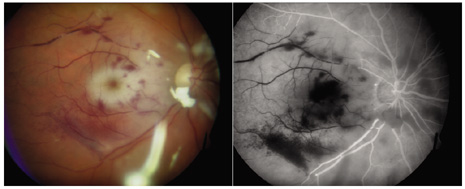

The typical clinical features of Candida endogenous endophthalmitis include fluffy yellow or white vitreous opacities and creamy white chorioretinal infiltrates (Fig. 13). Anterior uveitis frequently accompanies the posterior segment findings. A large macular abscess and pseudohypopyon formation (layering of inflammatory material under the internal limiting membrane of the retina) is not uncommon in cases of endogenous Aspergillus infection.25

Fig. 13. Endogenous endophthalmitis caused by Candida species. The patient, with no previous ocular surgery, presents with prominent white vitreous infiltrates typical of Candida species in a patient with systemic candidiasis.

When Aspergillus infection is suspected, aggressive local ocular therapy including vitrectomy and intravitreal amphotericin B is usually indicated.25 Successful treatment in Aspergillus endophthalmitis cases can be accomplished, but the occurrence of a macular abscess may reduce central vision on a permanent basis (Fig. 15). Because an intraocular Aspergillus infection is frequently associated with other organ involvement, particularly cardiac valve vegetation, a comprehensive systemic evaluation is mandatory, and systemic therapy is indicated in most cases.

Fig. 15. Endogenous fungal endophthalmitis. Left: Patient with history of intravenous drug abuse presents with progressive visual loss in the right eye. Marked retinochoroidal infiltrate is identified in the posterior pole. The patient was treated with pars plana vitrectomy and injected with amphotericin B 5 μg. Right: Aspergillus species was isolated from the vitreous specimen. Final visual acuity was 20/200 because of prominent chorioretinal scarring in the macula following treatment.